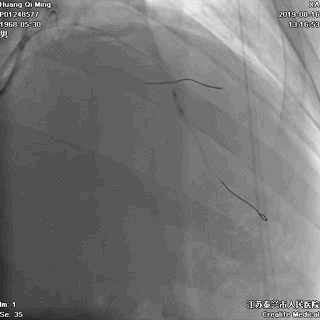

2.0*25 药物洗脱球囊,8atm*60秒释放药物

2.5*25 药物洗脱球囊,8atm*60秒释放药物

术后即刻效果满意